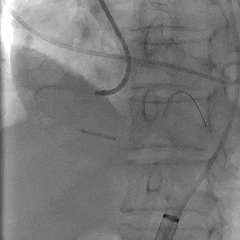

瓣膜初始定位

第一次释放,瓣膜位置偏高,选择回收

第二次瓣膜释放

造影评估,瓣膜位置可

右侧位造影,瓣膜深度可

多角度评估,瓣膜位置可,少量瓣周漏

脱钩后造影,瓣膜无位移,可见瓣周漏

20mm球囊后扩,瓣膜形态改善

后扩后评估,可见少量瓣周漏

最终瓣膜位置稳定